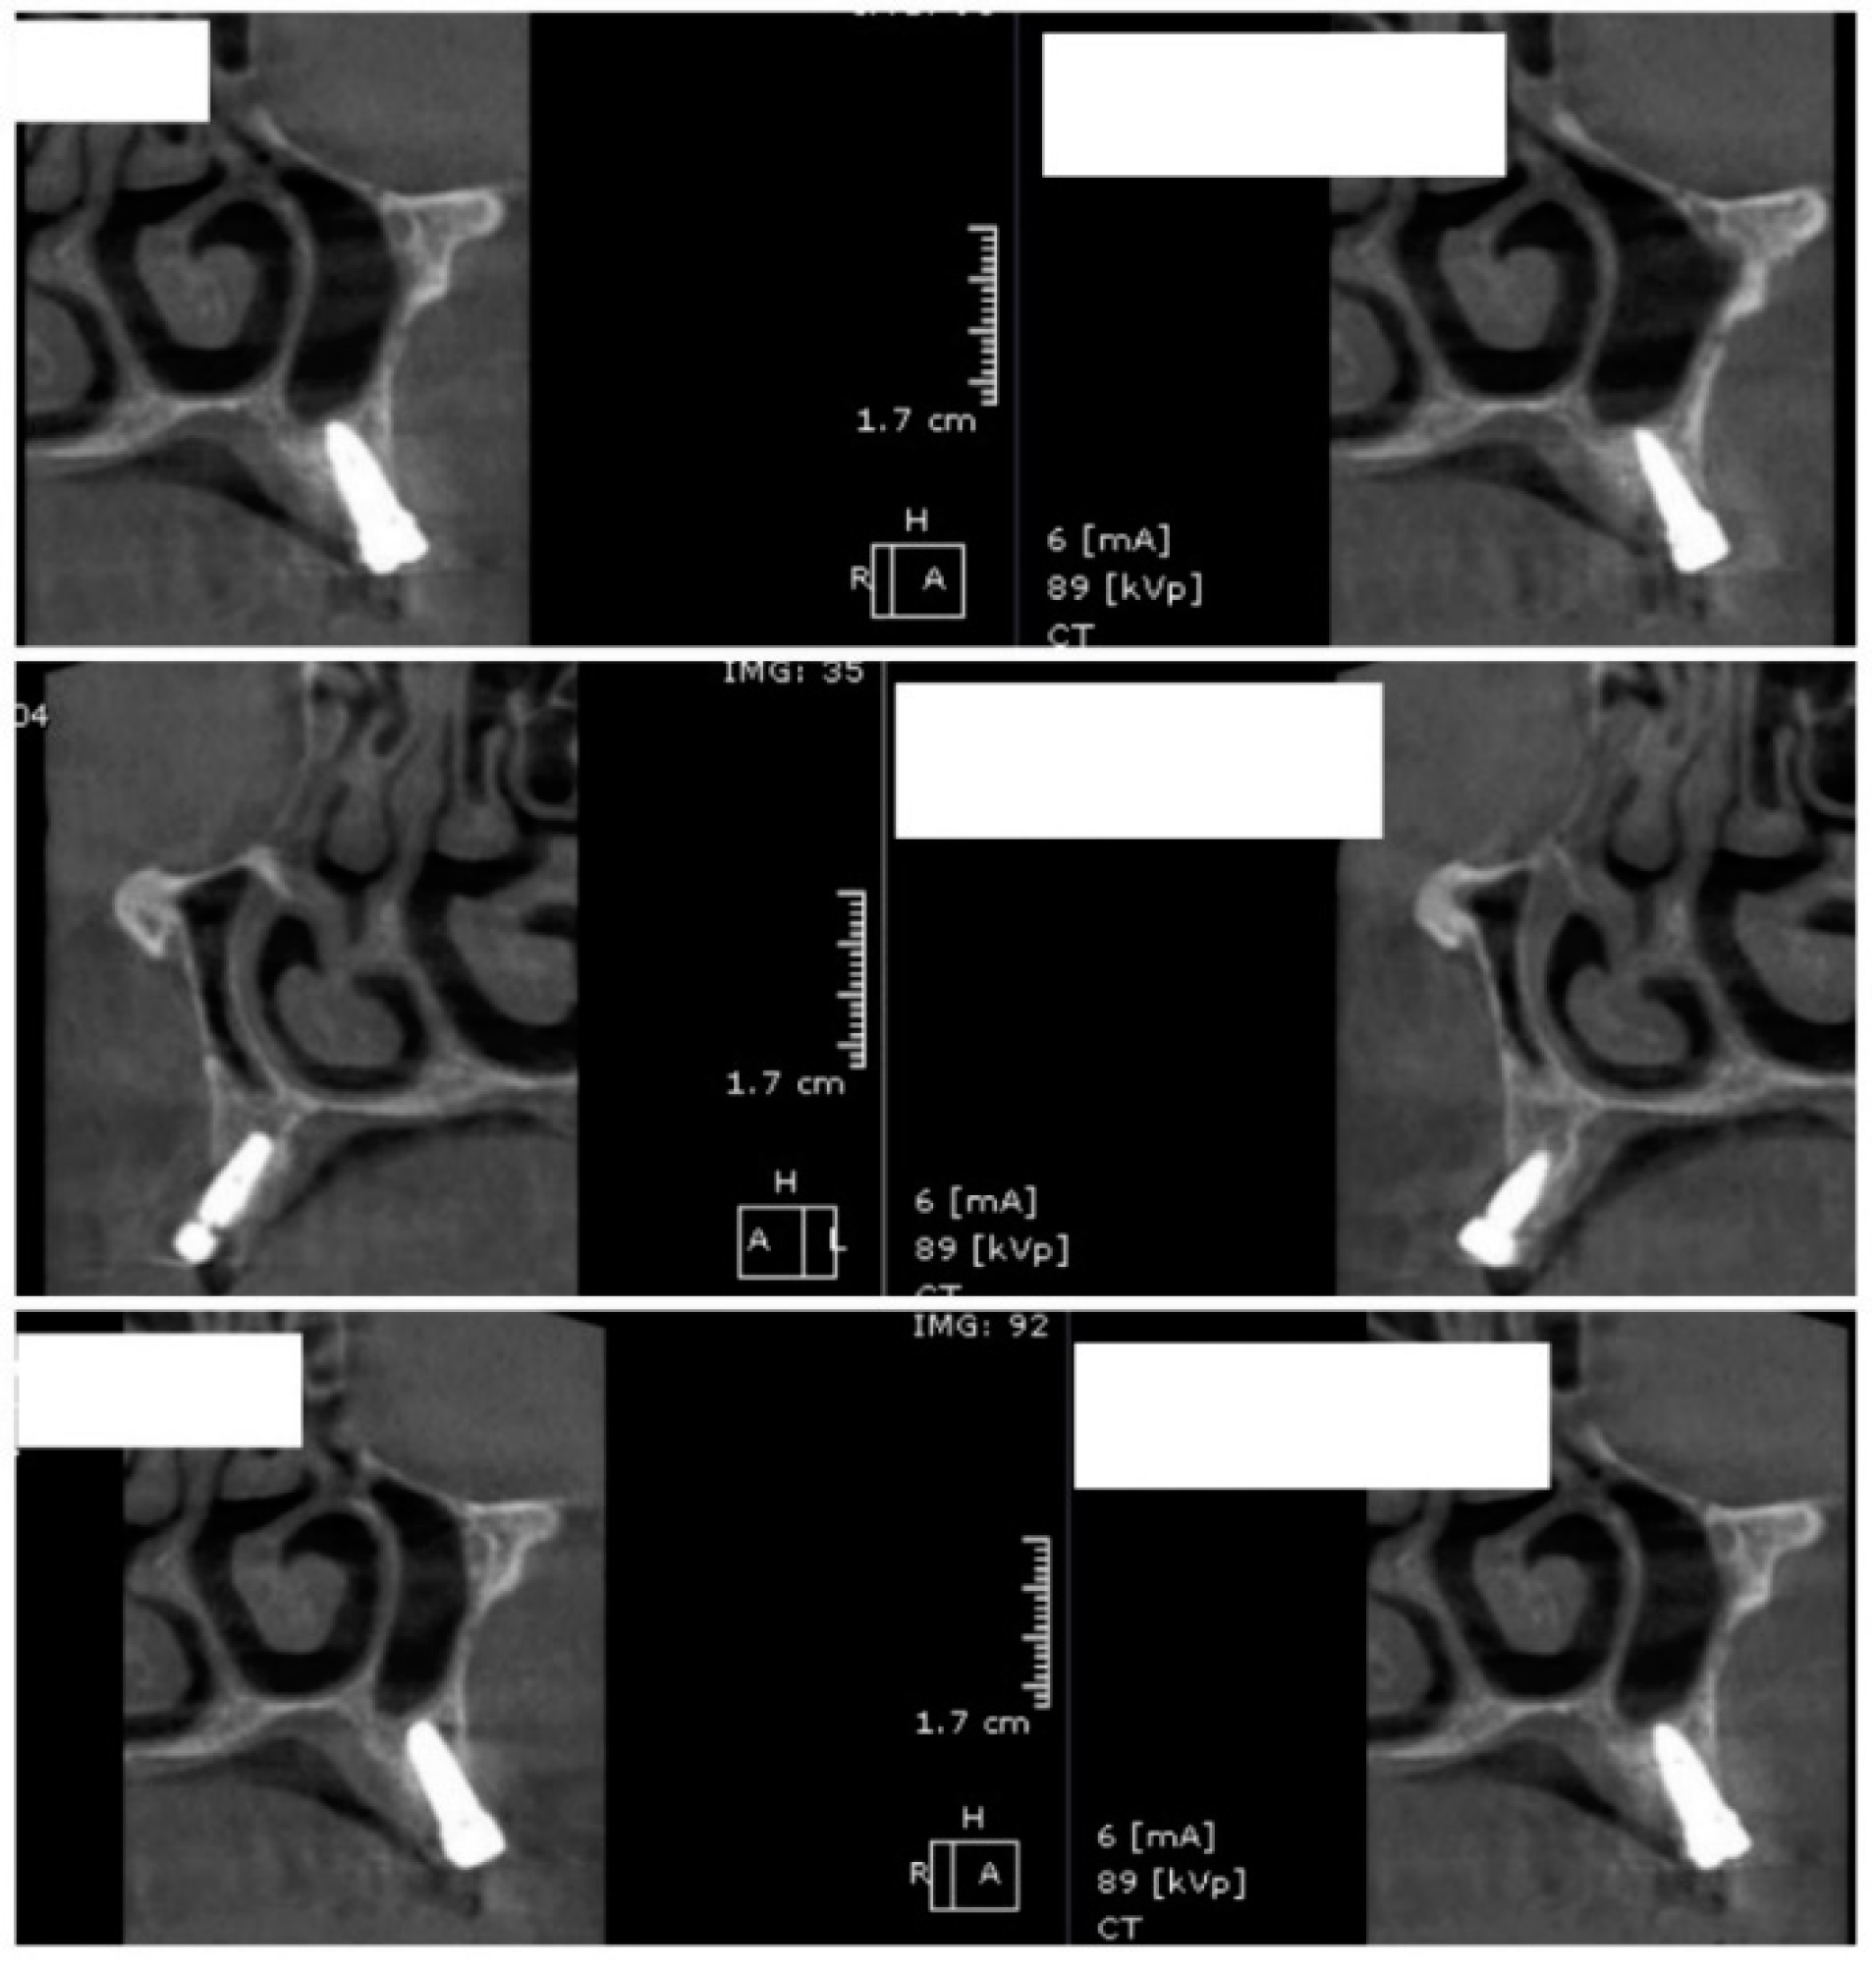

Image showing the bone density measured in Hounsfield units (HU) as well as the standard deviations of the volume.

Each voxel of the CBCT volume is characterized by a CT number, expressed in HU (Hounsfield Units). The software displays the mean value of the CT numbers of the constituent voxels and the standard deviation of these CT numbers (Figure 5).

In the next phase of the study, after a healing period of 60 days, new measurements regarding bone density were recorded (Figure 12 and Figure 13). To avoid the metal artifact/beam hardening effect created by implants, new measurements were recorded at a 2 m distance from the implant site.